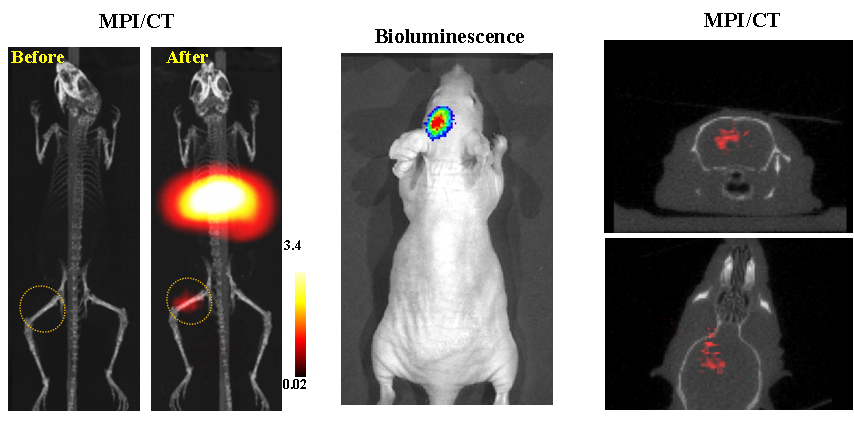

今年二月份,宋国胜教授与斯坦福大学饶江宏教授合作,通过系统的研究获得了影响磁性粒子成像信号的作用规律和关键原理,开发了新型磁性粒子探针---FeCo合金粒子,并首次应用于磁性粒子成像(MPI)。该造影剂在极低含量时(5 ng)仍具有很强的造影效果。这意味着,未来在进行人体成像时,可以使用更小剂量的造影剂,从而避免高剂量造影剂引起的肾肝损伤。基于MPI的直接成像原理,我们可以对造影剂进行正相和无背景干扰的活体成像,极大地提高信噪比。这项技术为肿瘤早期诊断、癌细胞示踪、脑中风、药物输送治疗、肺部灌注成像、胃肠出血、神经退行性疾病、磁热治疗等在活体中的可视化研究,提供了强有力的手段。相关研究成果以H视频

为第一单位发表在Nature 子刊《Nature Biomedical Engineering》。该期刊是“生物医学工程”的顶级期刊。宋国胜教授为该论文的共同通讯作者。